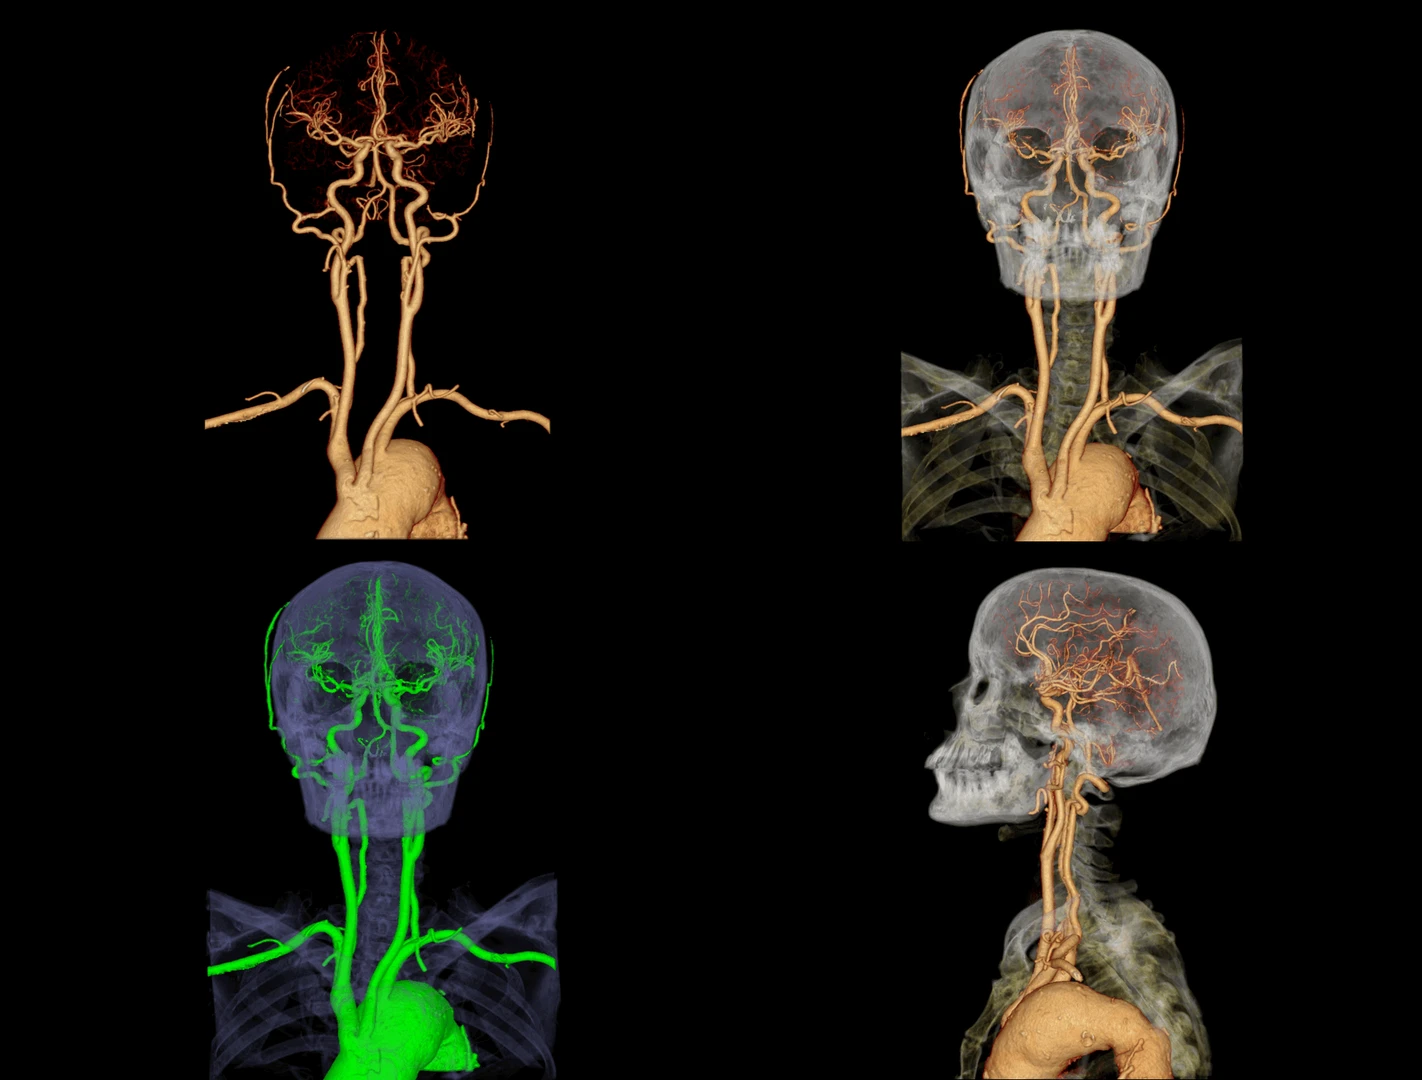

- Neurología: estudio de cerebro, columna y médula espinal

- Angio-TAC: sistema vascular